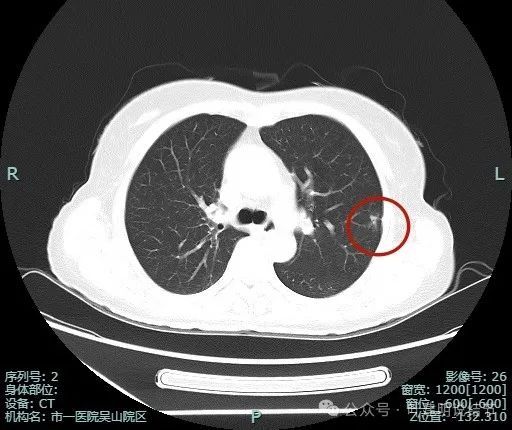

这种混合密度影像像浸润的结节缘何病理仍是原位癌伴微浸润?是否藏着混合磨玻璃结节是原位癌的奥秘!

病史摘要:69 岁男性患者,主因体检发现左肺部占位 2 年余就诊。2 年余前当地医院体检胸部 CT 提示左肺结节,当时有咳嗽咳痰,为白色粘痰,无其他不适,当地医院建议复查。2 年来症状同前,2024 年 12 月 3 日复查胸部 CT 提示左肺上叶部分实性小结节,考虑 MIA 或 IAC,现无明显不适,为求手术治疗入院。诊疗过程:体格检查未提及。辅助检查胸部 CT 提示相关结节情况